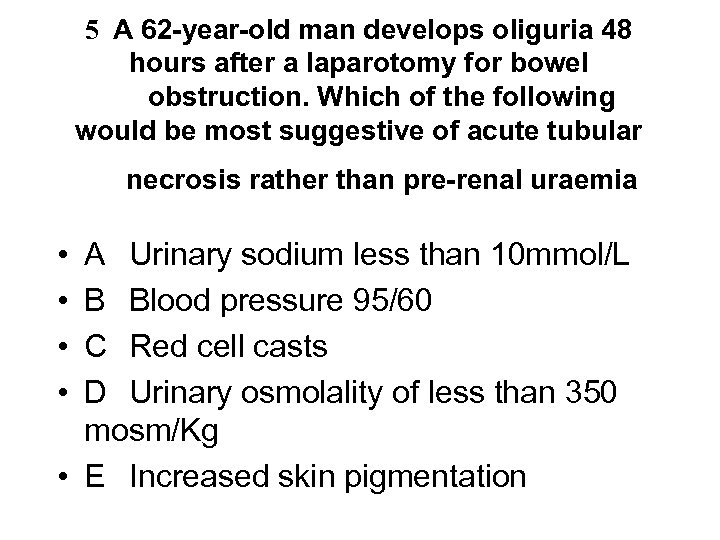

5 A 62 -year-old man develops oliguria 48 hours after a laparotomy for bowel obstruction. Which of the following would be most suggestive of acute tubular necrosis rather than pre-renal uraemia • • A Urinary sodium less than 10 mmol/L B Blood pressure 95/60 C Red cell casts D Urinary osmolality of less than 350 mosm/Kg • E Increased skin pigmentation

5 A 62 -year-old man develops oliguria 48 hours after a laparotomy for bowel obstruction. Which of the following would be most suggestive of acute tubular necrosis rather than pre-renal uraemia • • A Urinary sodium less than 10 mmol/L B Blood pressure 95/60 C Red cell casts D Urinary osmolality of less than 350 mosm/Kg • E Increased skin pigmentation

5 A 62 -year-old man develops oliguria 48 hours after a laparotomy for bowel obstruction. Which of the following would be most suggestive of acute tubular necrosis rather than pre-renal uraemia • • A Urinary sodium less than 10 mmol/L B Blood pressure 95/60 C Red cell casts D Urinary osmolality of less than 350 mosm/Kg • E Increased skin pigmentation

5 A 62 -year-old man develops oliguria 48 hours after a laparotomy for bowel obstruction. Which of the following would be most suggestive of acute tubular necrosis rather than pre-renal uraemia • • A Urinary sodium less than 10 mmol/L B Blood pressure 95/60 C Red cell casts D Urinary osmolality of less than 350 mosm/Kg • E Increased skin pigmentation

Incipient v established ATN • Incipient (tubules still function) U/P osmolality • >1. 5 Urine Na • <20 mmol/l Urine Osm • 350 -1000 m. Osm/kg • Established (tubules don’t function) • <1. 1 • >40 mmol/l • <350 m. Osm/kg NB - red cell casts are a feature of active GN not ATN - BP 95/60 mm. Hg reflects volume depletion or shock not necessarily ATN - skin pigmentation is a feature of CRF not ATN Nephrologists don’t use these criteria at all!

Incipient v established ATN • Incipient (tubules still function) U/P osmolality • >1. 5 Urine Na • <20 mmol/l Urine Osm • 350 -1000 m. Osm/kg • Established (tubules don’t function) • <1. 1 • >40 mmol/l • <350 m. Osm/kg NB - red cell casts are a feature of active GN not ATN - BP 95/60 mm. Hg reflects volume depletion or shock not necessarily ATN - skin pigmentation is a feature of CRF not ATN Nephrologists don’t use these criteria at all!